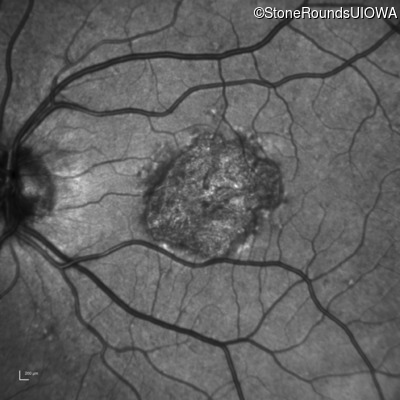

Infrared Fundus Photograph - Right - 20/40 +1 sc

Exemplar